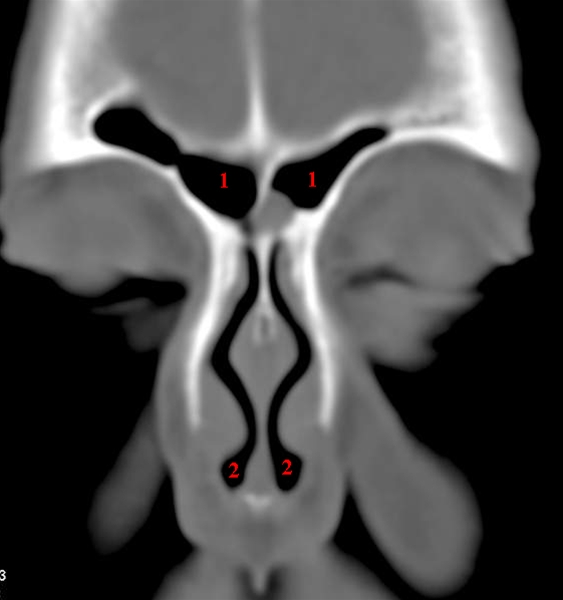

Sinus frontalis, coronal, CT

CT-snit i coronalplan gennem pandehulen (sinus frontalis) (1) og forreste del af næsen (2).